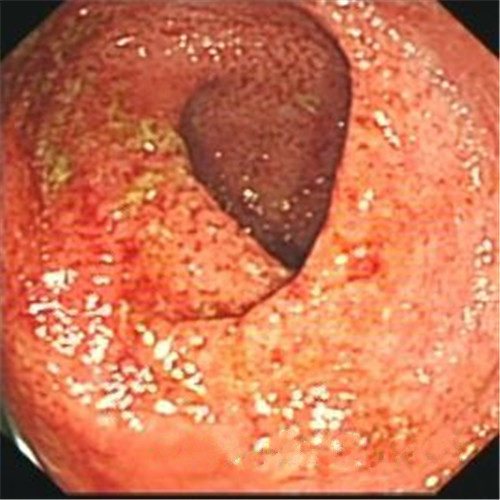

潰瘍性結腸炎治療前後對比